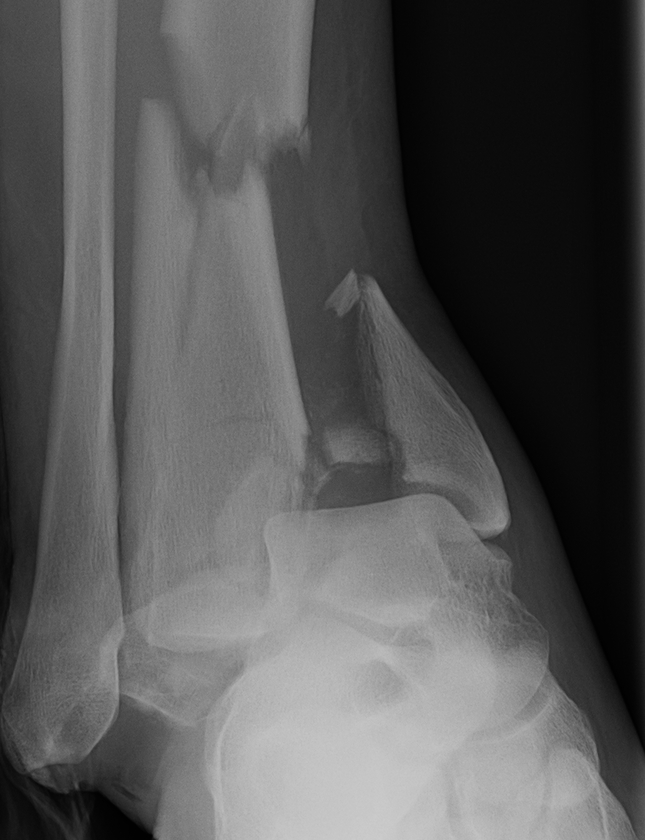

Tibial Plafond Pre External Fixator APTibial Plafond Pre External Fixator LateralTibial Plafond Post External Fixator APTibial Plafond Post External Fixator Lateral

Severe Tibial PlafondAnterolateral fragment and valgus injuryTibial Plafond External Fixator